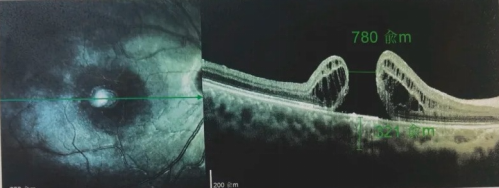

由于自身患有頸椎病,每次術后長期的趴睡都讓他痛苦不堪。為了尋求更好的治療,吳爺爺來到廈門大學附屬廈門眼科中心,找到了眼外傷及眼底病2科的李海波博士后。此時,吳爺爺右眼的黃斑裂孔已經持續(xù)擴大到780μm,演變?yōu)殡y治性的大裂孔。

黃斑裂孔,尤其是難治性、反復手術失敗的大裂孔,一直都是眼底外科的棘手難題。傳統(tǒng)手術核心步驟是剝除后極部內界膜,再利用眼內填充的氣體或硅油頂壓,結合患者長時間嚴格的俯臥位(趴睡),促使裂孔邊緣貼合、神經組織重新“搭橋”愈合。

但是對于反復手術的患者,黃斑區(qū)域的內界膜可能已經被剝除殆盡,沒有足夠健康的“橋接”材料;另外,長期俯臥位并不舒適,患者依從性較差,尤其是老人和小孩,容易影響治療效果。

面對像吳爺爺這樣后極部無健康內界膜可用的難治性大裂孔,以及自身患有基礎病,不適合術后長期趴睡的情況,又該如何解決呢?

經過完善的術前檢查和專業(yè)評估后,李海波博士后決定采用創(chuàng)新的治療方案——SPOT 技術輔助下遠周邊移植自體內界膜覆蓋,為他進行治療,手術在20分鐘內順利完成。